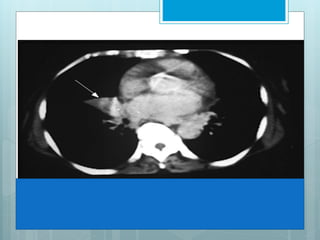

This image shows complete opacification of most of left upper lobe. When bronchi

remain aerated, they are seen as branching lucencies called air-bronchograms. This

image represents infectious pneumonia, limited by major fissure, resulting in a sharp

border.

This image showscomplete opacification of most of left upper lobe. When bronchi remain aerated, they are seen as branching lucencies called air-bronchograms. This image represents infectious pneumonia, limited by major fissure, resulting in a sharp border.